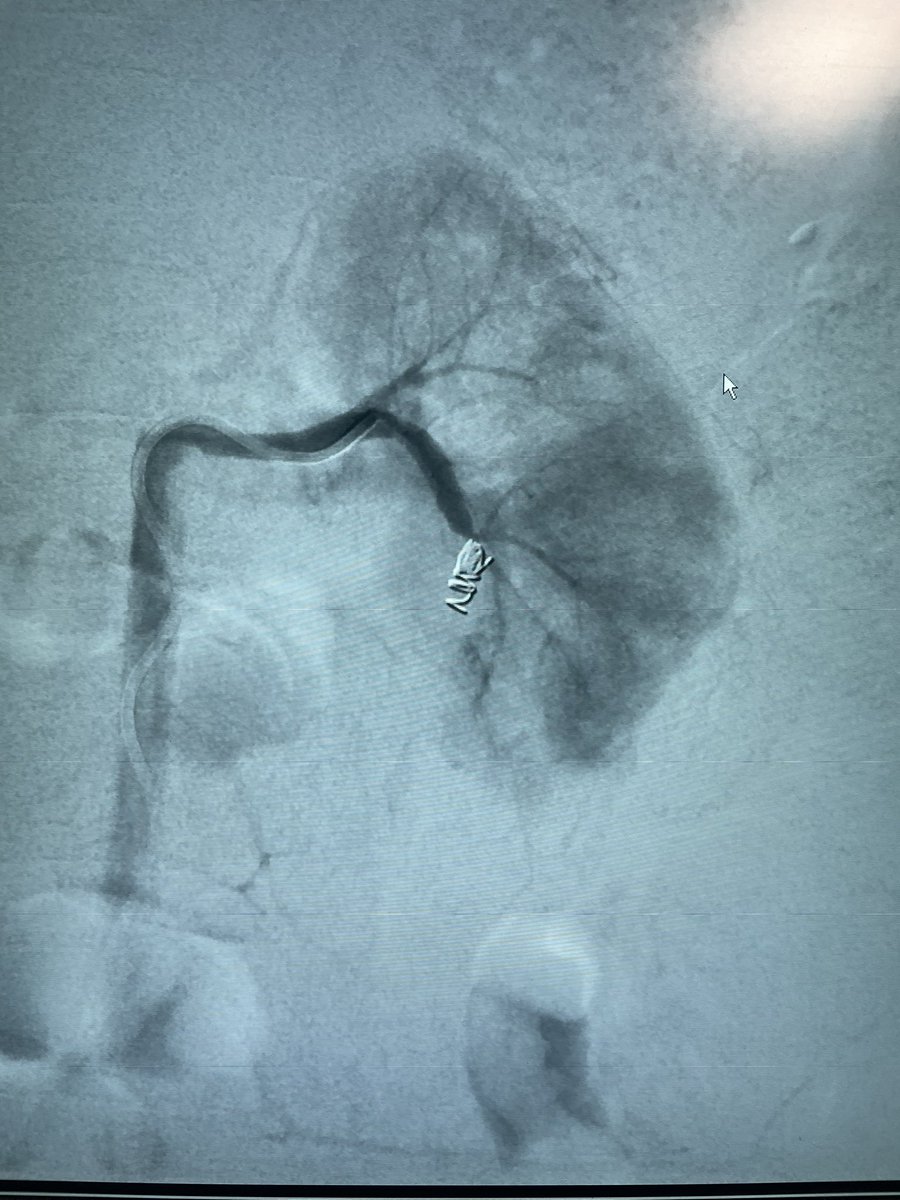

Lower GI Cecal bleeding, scope failed to manage, superselective coil embolization was performed. Hematochezia stopped. Inotropes were off.